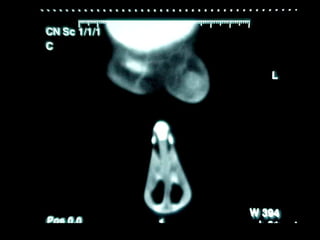

Mucormicosis

ntroducción.

Con este término, nos referimos a un grupo de micosis causadas por hongos

del orden Mucorales. La mayoría de los casos se presenta en personas con

factores de oportunismo severos como diabetes mellitus descompensada,

leucemia, o cáncer. Son infecciones graves que pueden causar la muerte; las

variedades clínicas más frecuentes son: rinocerebral, pulmonar, digestiva y

cutánea primaria. Las infecciones causadas por hongos del orden Mucorales,

generalmente se adquieren por vía respiratoria ya que las esporas de los

hongos se encuentran en el ambiente, aunque en las formas cutáneas

primarias, la infección se adquiere por solución de continuidad.

La paciente falleció a las 24 horas de internamiento por trombosis del seno